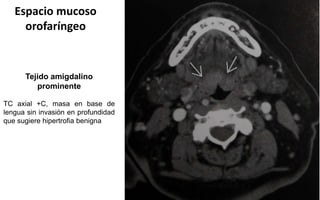

orofaríngeo

Tejido amigdalino

prominente

TC axial +C, masa en base de

lengua sin invasión en profundidad

que sugiere hipertrofia benigna